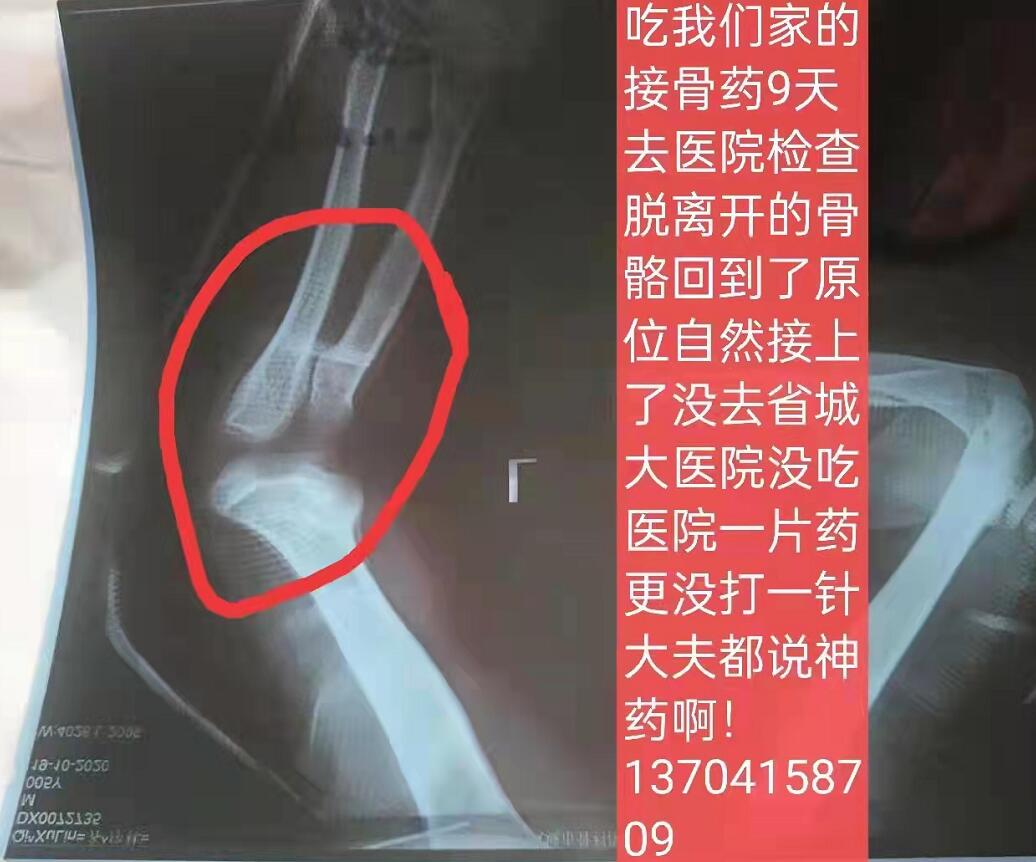

5、自然接骨药。